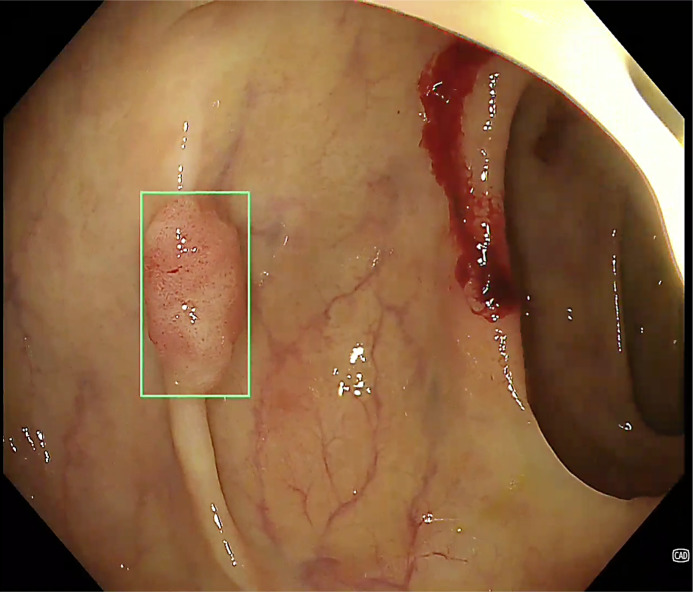

结肠镜检查在降低结直肠癌发病率和死亡率方面具有至关重要的作用。开发不同的人工智能(AI)系统,进一步提高其质量保证(计算机辅助质量改进,CAQ),病变检测(计算机辅助检测,CADe)和病变表征(计算机辅助表征,CADx)。有研究调查了这些人工智能系统在标准结肠镜检查的不同领域中的作用。方法:在这篇最新的叙述性综述中,我们总结了目前的证据,讨论了现有的局限性,并探讨了人工智能在结肠镜检查中的未来发展方向。结果:CAQ通过实时反馈和质量监测系统提高结肠镜检查质量,但由于训练数据集较小和方法不同,研究结果不一致。CADe提高了腺瘤的检出率,降低了腺瘤的漏检率,但也存在假阳性、不必要的息肉切除术、潜在的内窥镜医师技能下降和成本效益等问题。CADx系统在区分息肉类型方面的结果和准确性参差不齐,其使用进一步受阻于对无梗锯齿状病变的不充分代表,以及缺乏与标准结肠镜检查进行比较的严格试验。结论:尽管人工智能辅助结肠镜检查的证据越来越多,但其潜在的缺陷和局限性可能会阻碍其在实际临床实践中的进一步实施。关于临床疗效、成本效益、责任和数据共享的长期数据是需要解决的关键领域。

Results: CAQ enhances colonoscopy quality through real-time feedback and quality monitoring systems, but the studies have inconsistent results due to small training datasets and varied methodologies. CADe increases adenoma detection rate and reduces adenoma missed rates, but there are concerns about false positives, unnecessary polypectomies, potential deskilling of endoscopists, and cost-effectiveness. CADx systems have mixed results and accuracies in differentiating polyp types, and its use is further hindered by inadequate representation of sessile serrated lesions and a lack of rigorous trials comparing it with standard colonoscopy.